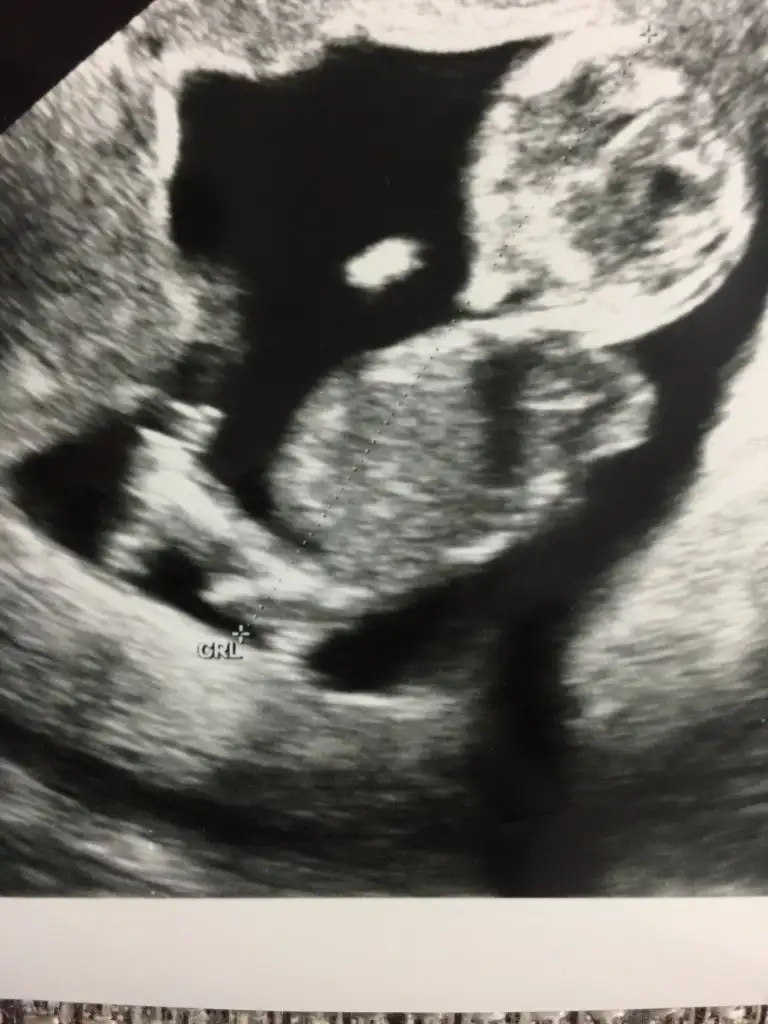

Kız gibi

Kız gibi gibi diyorum başka usg varmı varsa tahmin ederimMerhaba ben de yorum alabilir miyim 11+5Eki Görüntüle 2546031 Eki Görüntüle 2546031

Kız canım2 görüntü içinde aynı şey demi canım, doktorunda biri kız biri erkek demiş

Evet öğrendim bugün kızım olacakmışTahminim kızdı ögrendinizmi

Saglıkla gelsin prensesEvet öğrendim bugün kızım olacakmıştahmininiz tuttu